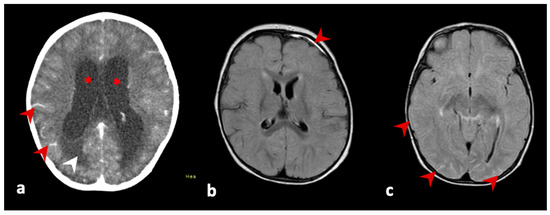

| 1; | female, 4 years of age | 20 July 2021, second dose | 25 August 2021 | 36 days | vomiting, hyporexia, non-responsiveness, weight loss of 3 kg, bradypnea, bradycardia. outcome: follow-up on 12 November 2021, no recurrence of signs and symptoms, without sequelae | leukocytes 17 cells/mm3, lymphocytes 86%, neutrophils 0%, protein 153 mg/dL, glucose 37 mg/dL, culture negative | brain CT: signs of hypertensive hydrocephaly (supra and infratentorial). brain NMR: increased dimensions of the ventricular system, with ependymal transudation and interstitial edema, in addition to hyperdynamic flow within the third and fourth ventricle and mesencephalic aqueduct. Note leptomeningeal enhancement in the base cysteines and cranial pairs. brain biopsy: granulomatous chronic inflammatory process with focal necrosis and histiocytes | plasma/serum: Ht 33.2%; Hb 11.8 g/dL; plat 304,000/mm3; leuko: 8810/mm3; 24.9% neutro; TB: 0.22 mg/dL; DB: 0.1 mg/dL, Cr: 0.4 mg/dL; AST: 21 UI/L; ALT: 11 UI/L; GGT: 10 UI/L; AP: 112 UI/L; INR 1.17; anti-CMV IgM negative and IgG positive; PCR for CMV: negative; anti-HIV I/II: negative; anti-Rubella IgM negative and IgG positive; FTA-abs negative; anti-toxoplasmosis IgM negative; anti-measles IgM negative; anti-EBV IgM negative; anti-HSV I/II IgM negative CSF: real-time PCR TB negative; anti-dengue IgM negative; anti-Zika IgM negative; anti-SLEV IgM negative; anti-WNV negative; anti-ROCV IgM negative; anti-CHIKV IgM negative | anti-YFV IgM positive in CSF |